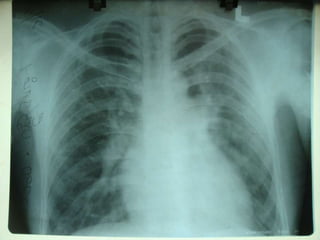

Laboratory StudiesGeneral laboratory studies are rarely helpful in sinus venosusatrialseptal defect (ASD).Imaging StudiesChest radiographyProminent right atriumProminent main pulmonary arteryIncreased heart size and pulmonary vascularity

Laboratory StudiesGeneral laboratorystudies are rarely helpful in sinus venosusatrialseptal defect (ASD).Imaging StudiesChest radiographyProminent right atriumProminent main pulmonary arteryIncreased heart size and pulmonary vascularity